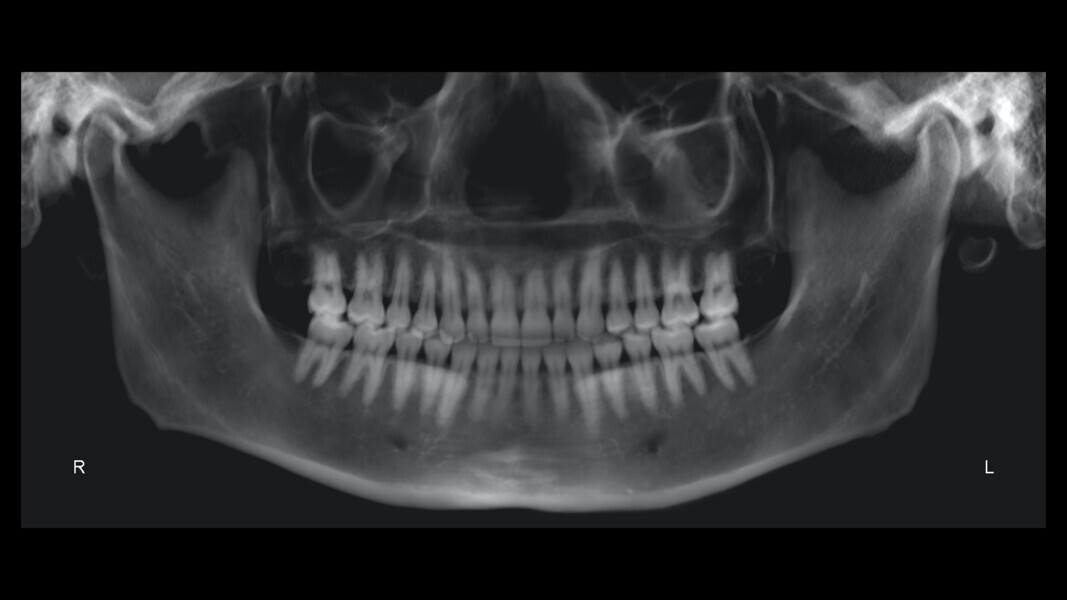

The panoramic radiograph confirmed the presence of all four third molar germs. Notably, there was advanced root resorption in the maxillary arch, although the overall periodontal health appeared good (Fig. 3). The cephalometric analysis showed a Class II skeletal pattern, a vertical growth tendency and posterior mandibular rotation. The maxillary and mandibular incisors were found to be slightly proclined (Fig. 4).

The panoramic radiograph showed prior extraction of all third molars, localised root resorption of several teeth, generally good periodontal health and an atypical condylar morphology, suggestive of temporomandibular joint (TMJ) remodelling or degenerative changes (Fig. 19). The cephalometric radiograph and tracing revealed a mesobrachyfacial skeletal pattern and a tendency towards a Class II skeletal pattern (Fig. 20).

The panoramic radiograph revealed the absence of third molars and good root morphology and parallelism (Fig. 37). The cephalometric radiograph and tracing indicated a Class III skeletal pattern tendency, characterised by a short cranial base and a long mandible. The maxillary incisors were retroclined, and the mandibular incisors were proclined (Fig. 38).